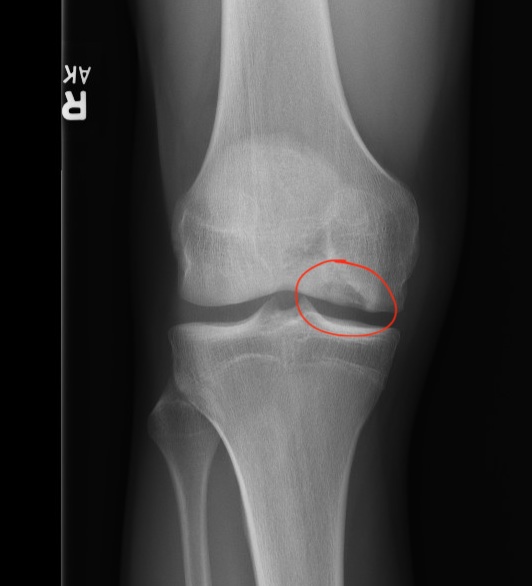

Osteochondritis dissecans (OCD) lesions of the knee can be difficult to treat. They most commonly occur on the lateral aspect of the medial femoral condyle (adjacent to the notch). They can also occur on the LFC, trochlea or patella. Below is an example of the typical location